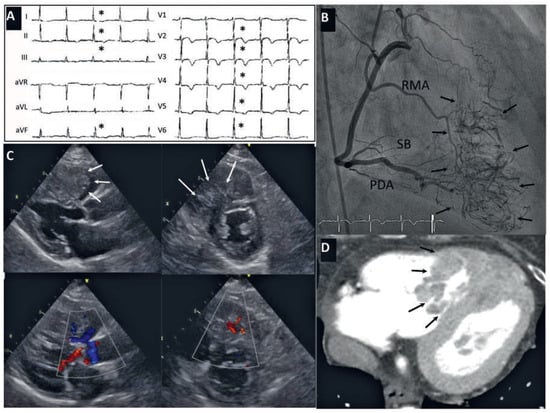

Case report